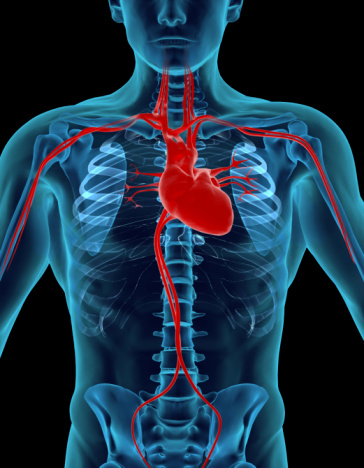

What a Broken Heart Means for Heart Health

A broken heart can do more than just cause emotional distress; it can actually comprise your heart health and cause physical heart problems. In fact, a broken heart brought on by an emotional stressor such as the death of a loved one or the discovery of a partners infidelity, can affect your heart health in ...click here to read more